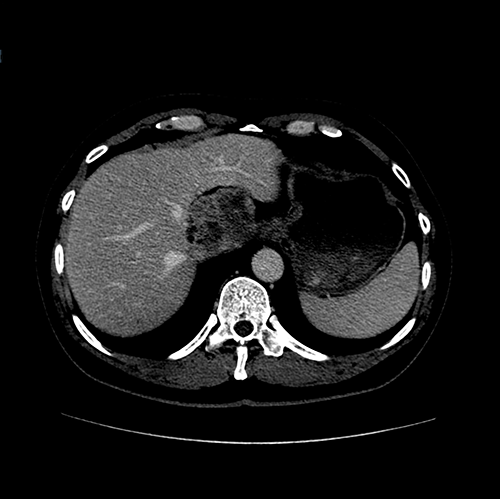

尾状叶肿瘤--尾状叶切除